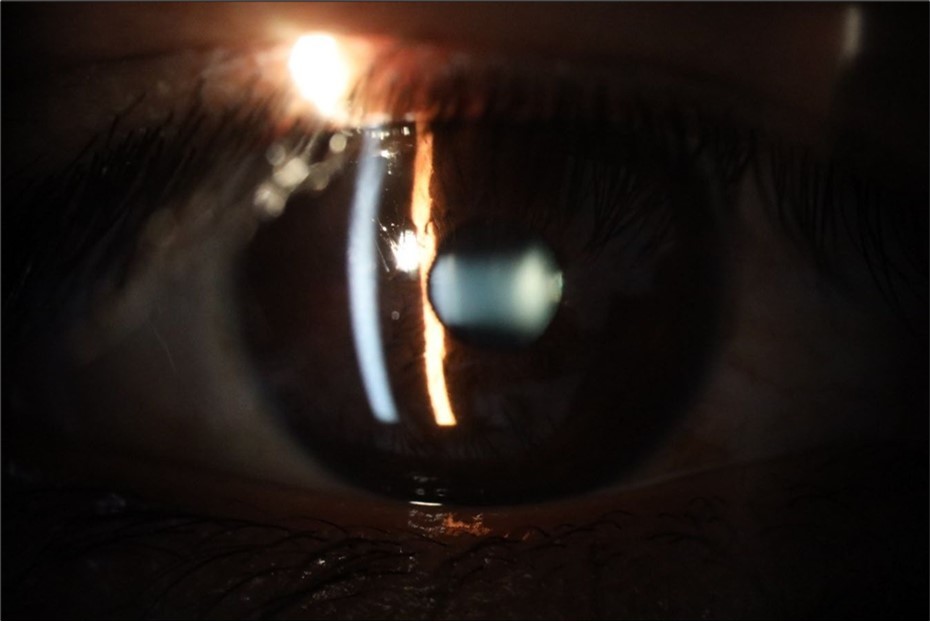

Figure 5.The slit-lamp photograph shows the anterior segment, relatively unscathed, in terms of transparent media (Cornea, crystalline and vitreous).

Figure 6.Slit-lamp examination showed a solution of continuity in the left temporal region, which fortunately only affected the conjunctiva and Tenon's capsule, while the sclera was unscathed.

Figure 15.The photograph shows better specular reflection, compared to the first day of the exam.

Figure 16.The anterior segment of the right eye shows the vitreous with greater transparency. The cornea and lens, as well as the anterior chamber, are in good condition.

Figure 25.Mirror reflection of the affected eye (right side), with good appearance. This indicates that the transparent media of the eyeball (Cornea, anterior chamber, lens, and vitreous) are in good condition.

Figure 26.The macrograph of the anterior segment of the right eye (affected) shows very good transparency of the cornea, anterior chamber, lens, and vitreous.

Figure 31.The photograph of the right eye shows an almost normal mirror reflection, as well as a better pupillary dilation.

Figure 32.The macro photograph of the right eye shows us a cornea, anterior camera, and crystalline lens in very good condition.